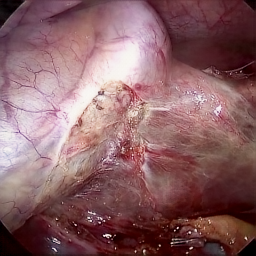

Refer to caption Refer to caption Refer to caption Refer to caption Refer to caption Refer to caption

Refer to caption (a) Input Refer to caption (b) case1 Refer to caption (c) case2 Refer to caption (d) case3 Refer to caption (e) Ours Refer to caption (f) Target

Figure 4: Ablation comparisons sampled from the DesmokeData and LSD3K datasets. The first two rows are from DesmokeData and the last two rows are from LSD3K. (settings: case1 = ADA+CrossGating, case2 = DHA+CrossGating, case3 = DHA+ADA).

IV-D Ablation Studies

To validate the effectiveness and individual contributions of the core components of our proposed RGA-Net, we conducted a series of ablation experiments on the DesmokeData dataset. We systematically analyzed the impact of our key designs: the DHA module, the ADA module, and the Cross-Gating (CG) mechanism for feature fusion. In these studies, we created several variants of our network by removing or replacing one component at a time and evaluated their performance. The quantitative results of these experiments are presented in Table II, and qualitative visual comparisons are shown in Fig. 4.

IV-D1 Effectiveness of the Dual-Stream Hybrid Attention Module

The DHA module is designed to capture both local surgical details and global illumination changes by combining shifted window attention with a frequency-domain processing branch. To ablate its effect, we replaced the DHA modules in the encoder with standard Swin Transformer blocks, thus removing the spectral pathway and the hybrid attention mechanism. As demonstrated in Table II, this variant experienced a significant drop in performance. This decline highlights the importance of integrating frequency-domain information, which is crucial for handling the complex light scattering caused by surgical smoke and restoring high-frequency textural details. The results confirm that the dual-stream approach provides a richer feature representation than spatial attention alone.

IV-D2 Effectiveness of the Axis-Decomposed Attention Module

We then investigated the contribution of the ADA module, which is employed in the decoder and latent space to efficiently process multi-scale features. We created a variant where the ADA modules were substituted with a more conventional self-attention mechanism without the block and grid axis decomposition. The results in Table II show a clear degradation in performance for this variant compared to the full model. This outcome validates that factorizing attention along two distinct axes allows the model to capture both fine-grained local patterns and long-range spatial dependencies more effectively and efficiently. The ADA module’s design provides a powerful yet computationally manageable way to model complex feature relationships during the reconstruction phase.

IV-D3 Effectiveness of the Cross-Gating Mechanism

Finally, we analyzed the efficacy of the cross-gating mechanism used for multi-scale feature fusion between the encoder and decoder. We replaced our CG blocks with a standard skip-connection method, specifically simple concatenation followed by a convolutional layer, as is common in many U-Net-based architectures. As shown in Table II, this change resulted in a substantial performance decrease. This finding underscores the superiority of the bidirectional feature modulation offered by our CG mechanism. Unlike simple fusion, cross-gating allows the encoder and decoder pathways to selectively amplify relevant features and suppress irrelevant information from each other, leading to a more refined and effective integration of multi-scale context, which is vital for high-quality image reconstruction.

In conclusion, the ablation studies comprehensively demonstrate that each of our proposed components—DHA, ADA, and CG—is integral to the overall performance of RGA-Net. The full model consistently outperforms all ablated variants, proving the synergistic benefits of our architectural design for the challenging task of surgical smoke removal.